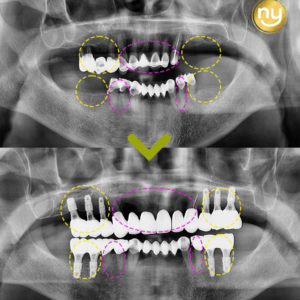

위 환자분은 충치가 많이 진행되어 신경치료한 치아를 사용하고 있었습니다.

하지만, 오랜 기간이 지나 치아 뿌리 끝에 염증이 생겨 발치를 권유받았는데요,

위 환자분은 재식술에 성공해 신경치료 후,

염증을 해결하고 내 치아를 살려 사용할 수 있게 되었습니다.

시술 4개월 후에도 정기적으로 내원하셔서 구강 상태를 확인해

문제없이 유지 및 관리하고 있습니다.